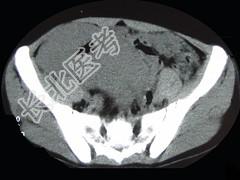

- 单项选择题男,22岁, 下腹部包块,1个月, 伴低热乏力,浅表淋巴结肿大, 影像检查如图,最可能诊断为 ( )

C、肠淋巴瘤